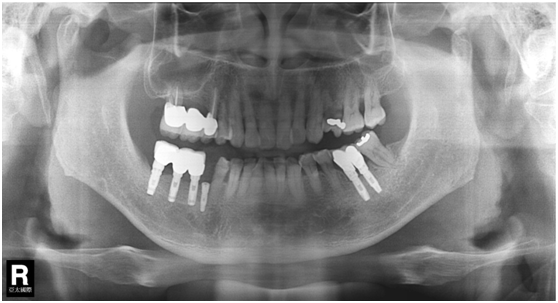

直到經過一年半後,於99/07/19又有明顯發炎,拍攝追蹤片,發覺連同更遠心的那顆植體的骨頭也破壞下降了

99/07/19

和患者積極溝通,由於患者神經管上的骨高度並不理想,建議積極移除中間兩顆有問題的植體重放,阻止發炎與骨破壞繼續下降;但患者想再追蹤。

患者於99/10期間因起床後有暈倒現象,住院後持續吃抗凝血劑,雖有發炎但不致於不舒服,因此一直不願積極處理;終於在100/03/1將兩顆植體移除,並於100/05/23回診評估再次植牙的條件。

100/05/23

於100/06/07重新放置兩顆植體

並於100/10/25將中間兩顆植體做二階接出

由於前後植體的高低差距太大,決定將中間兩顆高度較為一致的植體假牙做連結,但前後兩顆做單顆假牙的設計。

100/11/21 補綴完成

目前植體周圍的組織都很理想健康並追蹤中。